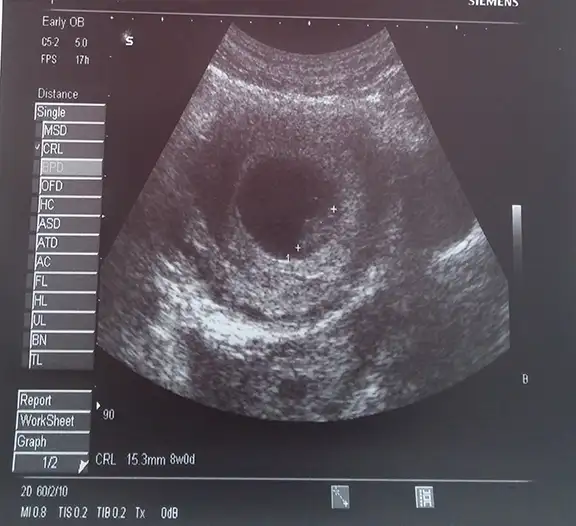

:KK200:Kizlar bebegime bakin çok tatlımasllah ellerimiz ayaklarimz ooluşmuş:KK36::KK9:

ya bu minyatur bi bebek cidden. Masalla:) 9. Haftadaymissin da tam kac hafta kac gunluk? Boyu ne kadar? Cok heyecanli:)

Ben de bugun mide bulantim icin gittim doktora. Normalde daha 2 hafta sonraydi kontrolum ama gitmisken ultrasonla baktik yine. 6 gunde 2 kati uzamis harika bi sey. Artik iyice belli oluyo. Bi dahaki gidisimizde boyle seninki gibi kocaman olmus olur ins.:)